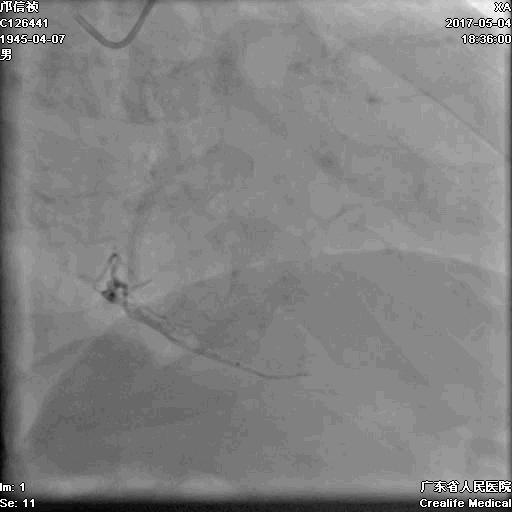

RRA:6F AL0.75 GC –RCA;

RFA:7F XB 3.5 GC—LCA 150cmcorsair

正向130cmFinecross微导管支持下尝试送PILOT150、Gaia 2导丝无法通过RCA闭塞段

SION导丝通过侧枝

逆向导丝:更换Gaia2

正向导丝:Gaia2,PILT150

正向导丝knuckle

2.5*15mm球囊扩张,逆向导丝尝试,但未能进入正向GC

1.正向2.5*15mm球囊扩张,Reverse CART

2.Guidezilla延长导管辅助下,逆向导丝进入正向GC